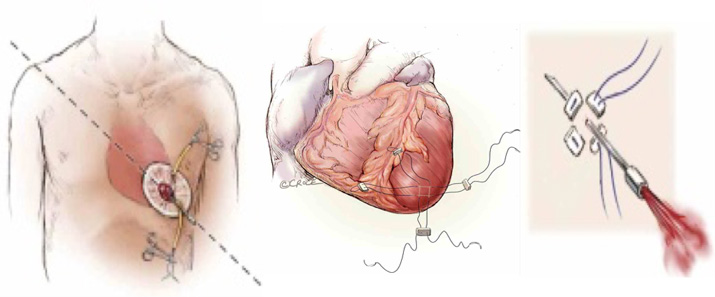

Αρκετές εταιρείες εργάζονται εντατικά για να τελειοποιήσουν την διακαθετηριακή προσθετική μιτροειδή βαλβίδα που συνεπτυγμένη πάνω σε καθετήρα προωθείται από την κορυφή της καρδιάς μετά από μικρή πρόσθια θωρακοτομή και εμφυτεύεται μέσα στην κατεστραμμένη.

Προσπέλαση από την κορυφή της καρδιάς μετά μικρή πρόσθια θωρακοτομή και προώθηση του καθετήρα που φέρει συμπτυγμένη την βαλβίδα.

Ο καθετήρας που φέρει την συμπτυγμένη βαλβίδα TWELVE και σχηματική απεικόνιση των σταδίων εμφύτευσης της βαλβίδας στην θέση της μιτροειδούς.